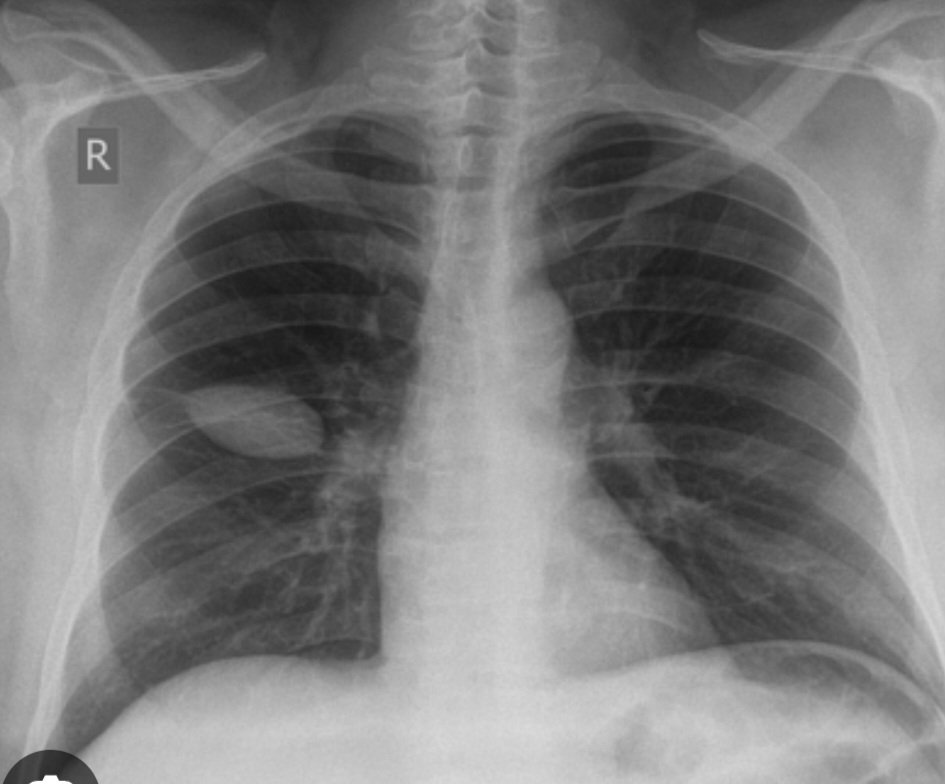

@PHANTOM TUMOR OF THE LUNG - Rare, Mass-like appearance on a lChest X-ray that's caused by fluid in the lungs. It's also known as a VANISHING TUMOR or pseudotumor.  CAUSES- CONGESTIVE HEART FAILURE, Fluid overload, Adhesions from previous pleuritis, Renal failure, and Hypoalbuminemia. adow on a chest X-ray that resembles a tumor  Located in the right-middle zone of the lung, but can also be on the left side  TREATMENT-Correcting the underlying heart condition and volume overload Taking diuretics to treat pleural effusion SIGNIFICANCE It's important to recognize phantom tumors to avoid unnecessary diagnostic tests and errors in therapy  They can relapse in patients with heart failure who experience recurrent decompensation  Related terms Interlobar or encysted effusion, Localized interlobar effusions, and Mass-like appearance of interlobar pleural fluid collection. #MedTwitter #MedEd #MedX